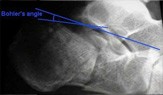

Bohler's angle